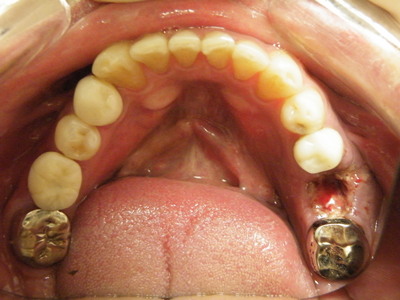

右下は昨日抜歯して人工骨とコラーゲンで再生した場所 2日でこの治癒状態 ここもインプラントにします